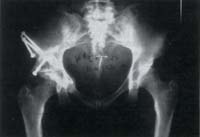

En cuanto a la lateralización, doce de los pacientes presentaron desplazamiento medial, 4 pacientes lateralización y 3 pacientes permanecieron sin cambios (figura 3).

Fig. 3. Radiografía de osteotomía de Ganz consolidada con adecuada corrección.